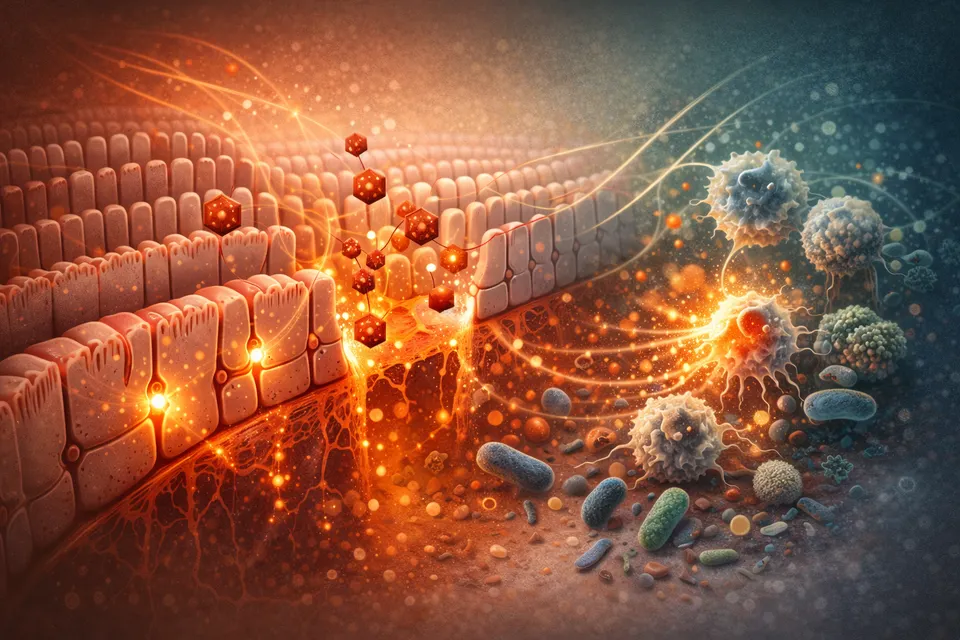

How the body rebuilds the barrier that decides what you absorb—and what you don’t.

How the body rebuilds the barrier that decides what you absorb—and what you don’t.